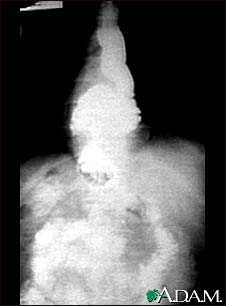

Hiatal hernia - X-ray

This x-ray shows the upper portion of the stomach protruding through the diaphragm (hiatal hernia).